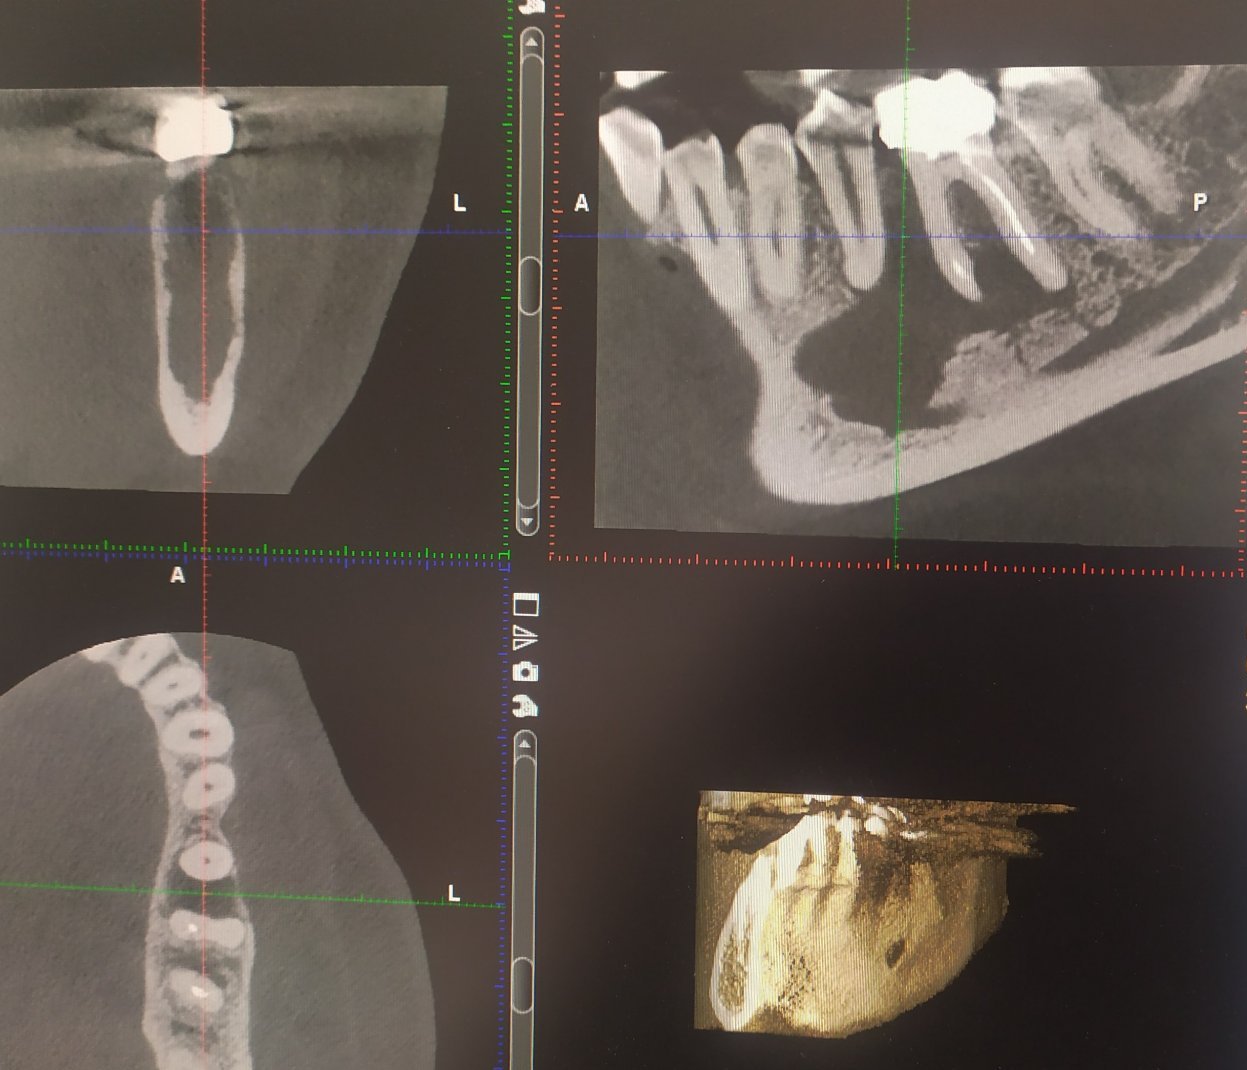

Това са снимки от скенера - преди лечението и след-

Скрит текст: